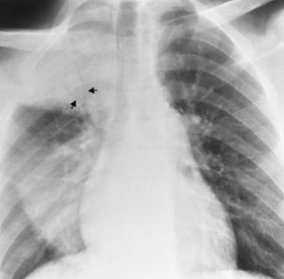

RA: primary tuberculosis (4 criteria)

lobar consolidation

enlarged hilar/nodes

the ghon lesion

pleural effusion

Describe the RA of tuberculosis with lobar consolidation

dense well-defined consolidations usually apical

(image shows consolidation in upper and lower lobes)